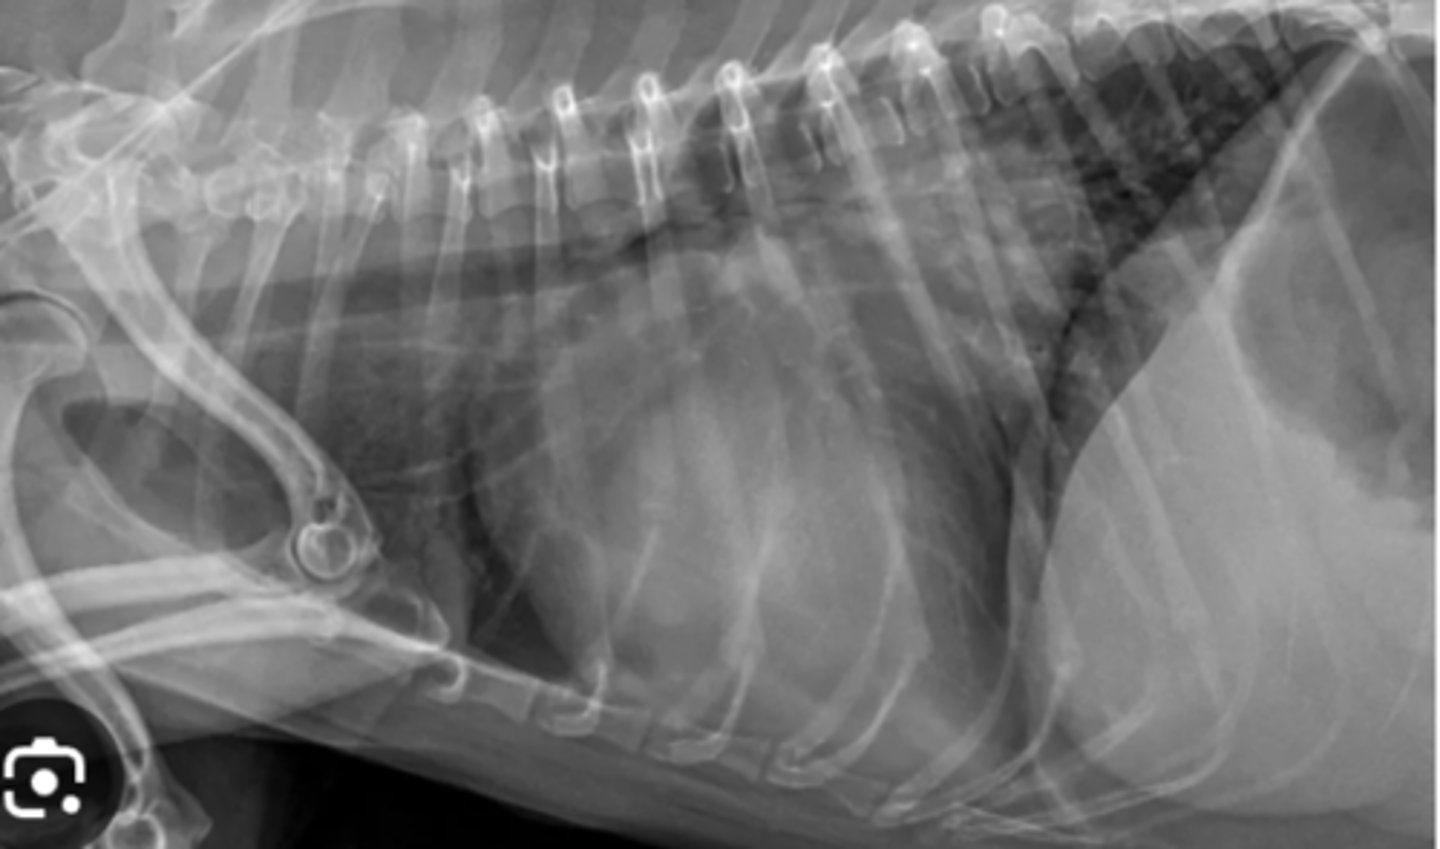

Use this image with this question "Rocky', a 4-year-old Gordon Setter, is presented with a rapid onset of dyspnea. Lung sounds are decreased. The owner is not much help but says "Rocky' was fine yesterday. Only one radiographic view is available, because the patient is distressed. What is your diagnosis based on this lateral radiograph?

Pleural effusion

Pneumothorax

Dog with dyspnea and radiograph shows heart lifted dorsally- what has caused this?